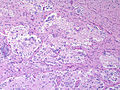

| Glioblastoma (WHO grade IV) | glial processes (esp. on smear), nuclear atypia (typical size var. ~3x, irreg. nuc. membrane, hyperchromasia), no Rosenthal fibres in the core of the lesion †, microvascular proliferation or necrosis | often enhancing (suggests high grade), usu. supratentorial, usu. white matter | usu. old, occ. young | very common, esp. glioblastoma | IDH-1+/-, GFAP+ | |

| Metastasis | sharp interface with brain, often glandular, +/-nucleoli, no glial processes | often cerebellular, well-circumscribed | usu. old | often suspected to have metastatic disease | TTF-1, CK7, CK20, BRST-2 |

Brain metastasis

Images

Glioblastoma: